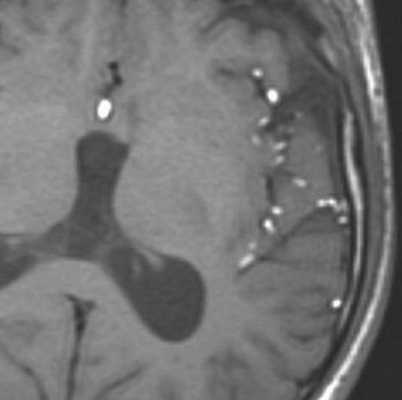

МРТ головного мозга. На мрт в аксиальной плоскости отмечается объемное образование внутреннего слухового прохода слева (стрелка), с четкими и неровными контурами, деформирующее окружающие структуры. После внутривенного введения парамагнитного контрастного вещества отмечается интенсивное и неоднородное его накопление образованием (изображение справа) — невринома.